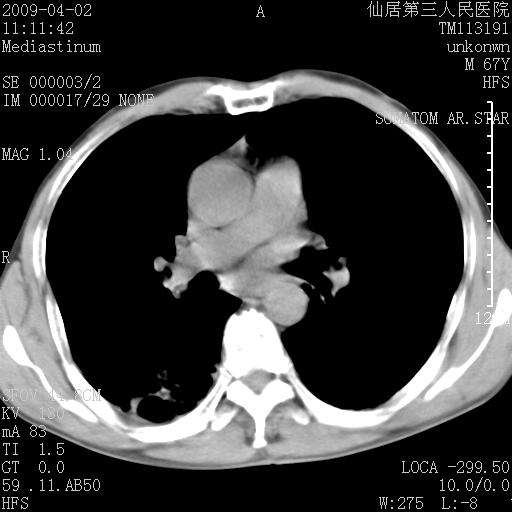

患者老年男性,乏力畏寒来诊,摄胸片示右下肺感染性病变,抗炎两周后复查胸片,无好转有进展。

后做ct平扫表现如下:

考虑右肺炎症可能性大,不除外细支气管肺泡癌

是否还要考虑肺间质纤维化,建议hrct扫描。

病灶呈蜂窝征,纵隔多个淋巴结肿大;肺泡癌需考虑

右肺下叶背段干酪性肺炎。请痰检[emb28]

我认为普通的感染应该可以除外,间质性肺炎可能性较大,但如何解释纵膈的淋巴结肿大呢

考虑双肺间质性改变(间质纤维化?)伴右肺下叶感染。